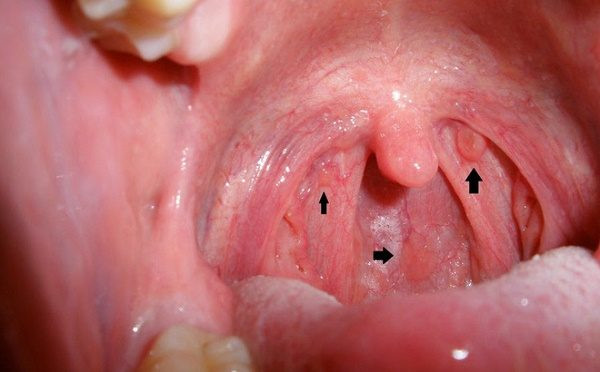

1. Người bị loét miệng lâu năm Đối với nhiều người, lở loét miệng là chuyện thường xuyên xảy ra. Nhiều khi chúng ta chỉ đơn giản là uống một số loại thuốc chống viêm, triệu chứng sẽ đỡ hẳn.

Đối với nhiều người, lở loét miệng là chuyện thường xuyên xảy ra. Nhiều khi chúng ta chỉ đơn giản là uống một số loại thuốc chống viêm, triệu chứng sẽ đỡ hẳn.

Thế nhưng, nếu triệu chứng lở loét miệng diễn ra thường xuyên thì chứng tỏ nó đã kháng lại nhiều loại thuốc và vi khuẩn có lợi, nếu không chú ý thì chúng ta có thể mắc bệnh ung thư miệng, cực kỳ nguy hiểm.

2. Người bị nhiễm virus HPV trong thời gian dài Tôi tin rằng đối với nhiều người, virus HPV còn tương đối xa lạ, nó thường ảnh hưởng đến cổ tử cung của chúng ta và dễ gây ung thư, nhưng bạn có biết không? Trên thực tế, nó vẫn là mối nguy hại lớn đối với khoang miệng của chúng ta.

Tôi tin rằng đối với nhiều người, virus HPV còn tương đối xa lạ, nó thường ảnh hưởng đến cổ tử cung của chúng ta và dễ gây ung thư, nhưng bạn có biết không? Trên thực tế, nó vẫn là mối nguy hại lớn đối với khoang miệng của chúng ta.

Nếu phát hiện sớm thì có thể điều trị tốt nhưng nếu bệnh nặng thì hiện tại, y học vẫn không có cách giải quyết, nhắc nhở mọi người chú ý.